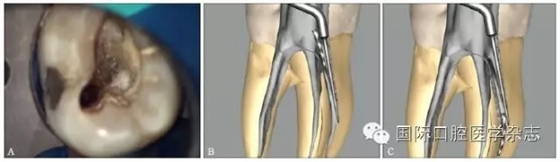

4.2.1 超聲技術(shù)取出分離器械 若選擇使用超聲技術(shù)取出根管內(nèi)分離器械,首先用小棉球堵住其他根管口,避免分離器械進(jìn)入其他根管內(nèi)(圖10A)。將工作尖的運(yùn)動振幅調(diào)整至較低檔,選擇較低的功率進(jìn)行操作。在到達(dá)分離器械冠方末端的直線通路與平臺已創(chuàng)建完成的基礎(chǔ)上,使超聲工作尖先在分離器械末端的一側(cè)局部來回運(yùn)動,輕柔地去除分離器械一側(cè)的牙本質(zhì),嘗試將超聲工作尖楔入分離器械與管壁之間,使分離器械震動,直至其“跳出”根管口(圖10B)。若局部運(yùn)動無法使分離器械松動彈出,則以逆時針方向圍繞分離器械四周輕輕移動,去除牙本質(zhì),逐步暴露其冠方末端。一般來說,分離器械會出現(xiàn)松動,最終沿其長軸方向旋出(圖10C)。

A:使用超聲技術(shù)前,用小棉球堵住其他根管口;B:首先用超聲工作尖在根管壁的一側(cè)局部來回運(yùn)動,直至分離器械跳出根管口;C:若局部運(yùn)動無法取出分離器械,則按逆時針方向圍繞分離器械周圍運(yùn)動,逐步暴露分離器械冠方的末端。

圖 10 用超聲技術(shù)取出根管內(nèi)分離器械

超聲技術(shù)作為經(jīng)典且有效地取出分離器械的方法之一,具有獨(dú)到的優(yōu)勢。超聲工作尖可以在顯微鏡直視下在根管內(nèi)運(yùn)動,且能夠不對稱地去除分離器械周圍的牙本質(zhì),若只在分離器械一側(cè)局部運(yùn)動即能取出分離器械,則有利于保存根管壁較薄一側(cè)的牙本質(zhì),減少牙本質(zhì)的損失。此外,當(dāng)器械分離于根管中下段甚至超出根尖孔,而分離器械較松時,可用超聲工作尖伸入根管內(nèi)分離器械旁邊,利用水流與超聲振動將分離器械帶出根管(圖11)。